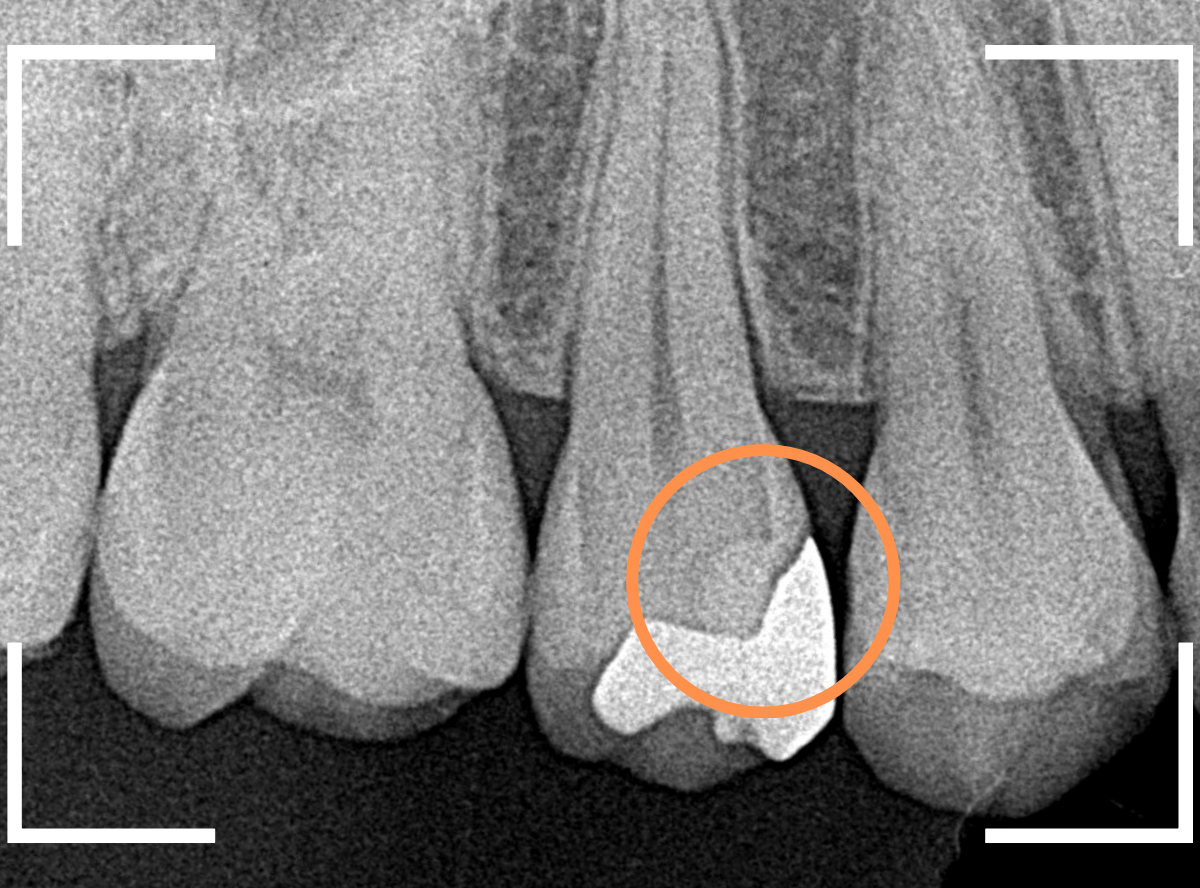

Case.25 深い虫歯の治療~無事にセラミック・インレーへ

今回は、上の奥歯が深くて広い虫歯になっていた方のケースです。

〇部が虫歯の部分です。

この写真からは深い虫歯があるのは想像つきません。

レントゲン写真で確認します。

青い線が神経、赤い線が虫歯の部分です。

前後の歯とも、かなり深く広い虫歯になっているのがわかります。